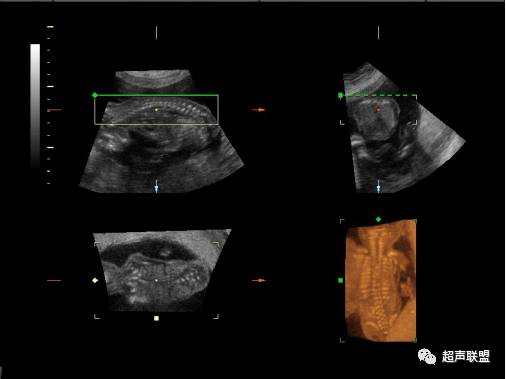

多层面成像应用

检查胎儿脊柱,,大脑和心脏连续的横断面.

从胎儿脊柱和脸的正中矢状面获取三维容积数据

脑的横断面在BPD平面获得一个三维容积数据

心的横断面在四腔心平面获得一个三维容积数据

斜面成像 OBVTM的应用

检查:胎儿脊柱,颚的冠状面

室间隔的“平面内切面”

骨骼的三维超声

80-100 % 的四肢远端,肋骨,锁骨可以显示

四肢: 矢状切面 /其它方向,以避免伪影遮蔽

肋骨: 横断或冠状面,从旁边开始扫描

锁骨: 横断或矢状面

肩胛骨: 矢状面